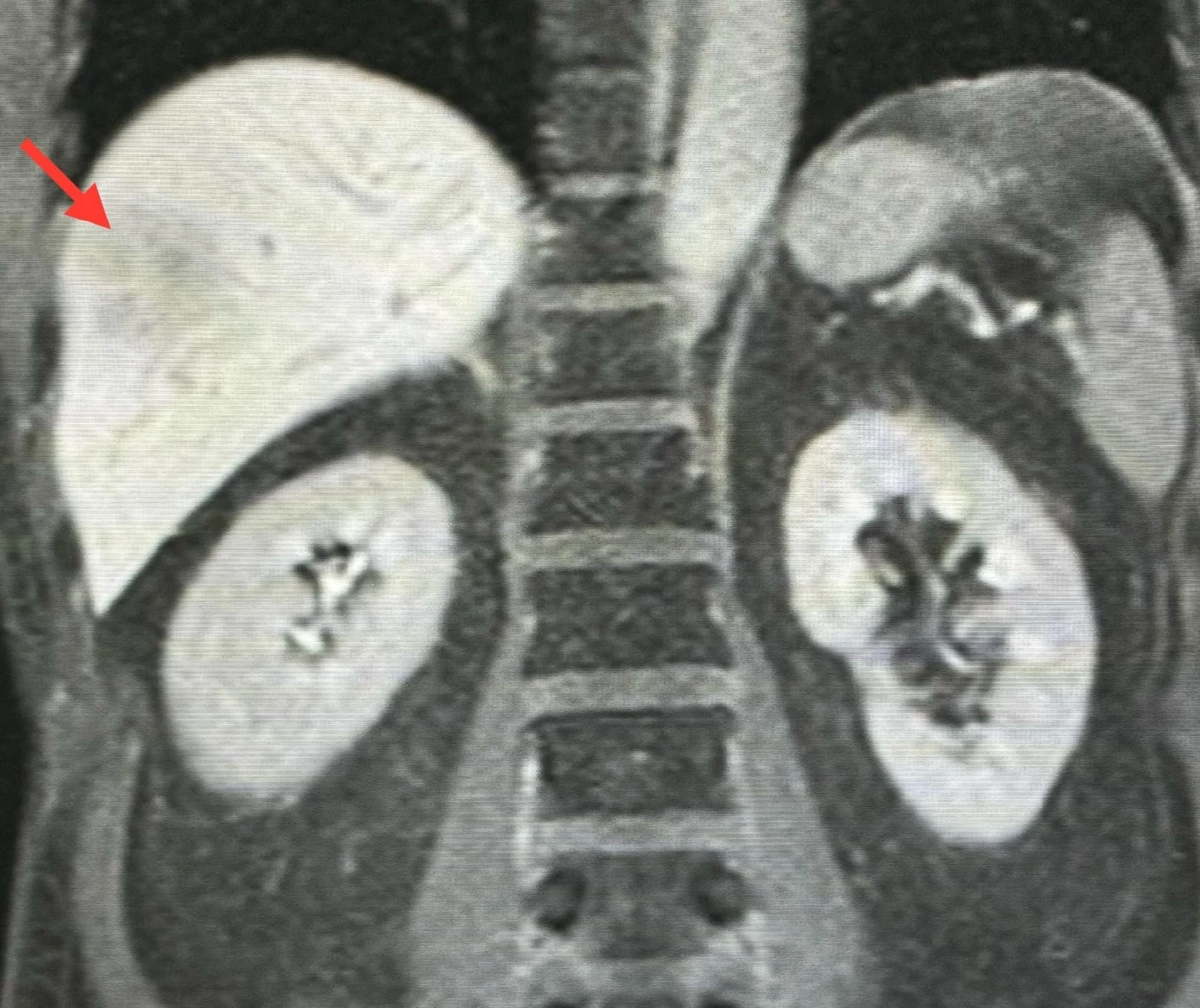

เจาะเลือดพบจำนวนเม็ดเลือดขาว 8,500 เซลล์ เป็นเซลล์ชนิด eosinophil สูงถึง 37% (ปกติไม่เกิน 5%) ค่าเอนไซม์ตับปกติ ค่ามะเร็งทุกตัวปกติ ตรวจเลือดไม่พบพยาธิสตรองจิลอยด์แอนติบอดี ตรวจอุจจาระไม่เจอพยาธิและไข่พยาธิ ทำอัลตราซาวด์ของตับพบก้อนขนาด 1.9 × 1.2 เซนติเมตรและ 0.9 × 0.8 เซนติเมตรในตับข้างขวา ปีที่แล้วทำอัลตราซาวด์ไม่พบก้อนในตับ ทำคลื่นแม่เหล็กไฟฟ้า MRI ของตับพบก้อนขนาด 2.8 × 2.4 × 2.1 เซนติเมตรและ 4.5 × 3.1 × 3.3 เซนติเมตรในตับข้างขวา

เจาะชิ้นเนื้อตับ ส่งตรวจพยาธิวิทยา พบฝีในตับประกอบด้วยเม็ดเลือดขาวชนิด eosinophil ไม่พบพยาธิ ไข่พยาธิ หรือมะเร็ง

วินิจฉัย : ฝีในตับสงสัยเกิดจากพยาธิใบไม้ในตับฟาสซิโอลา (Fascioliasis) มากกว่าจากพยาธิใบไม้ในตับโอพิสธอร์คิส (Opisthorchiasis) ส่งเลือดตรวจหาแอนติบอดีต่อพยาธิใบไม้ในตับฟาสซิโอลา (Fasciola)